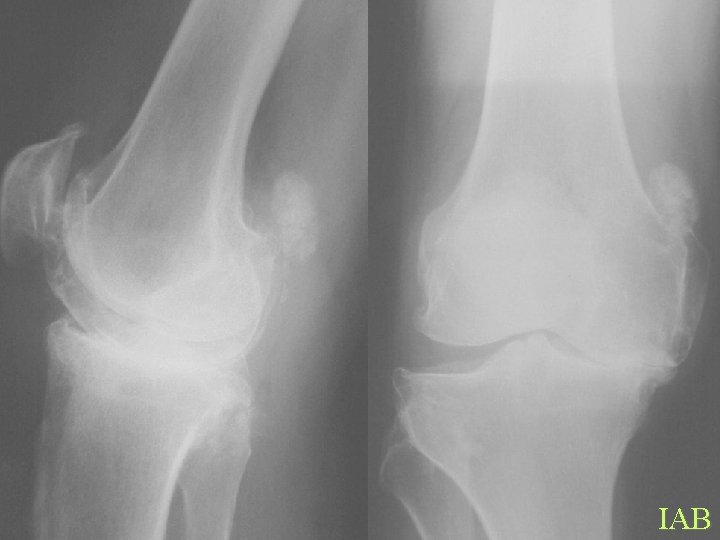

Calcification By site Periarticular • Hyperparathyroidism • • Renal osteodystrophy Milk alkali syndrome Hypervitaminosis D Collagen vascular disease • Exclude intraarticular

IAB

Calcification By site Articular cartilage • Osteoarthrosis • • CPPD HADD Hyperparathyroidism Haemochromatosis